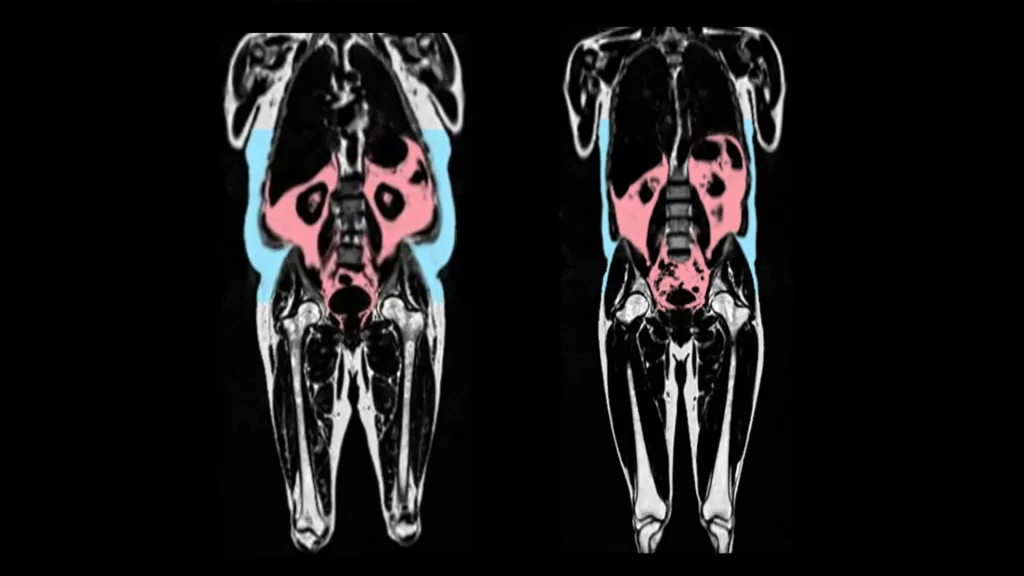

Hidden fat wrapped around organs, known as visceral fat, has now been linked to faster heart aging. Using AI and imaging from more than 21,000 people in the UK Biobank, scientists found that this invisible belly fat accelerates stiffening and inflammation of the heart, while fat stored around hips and thighs may actually protect women.